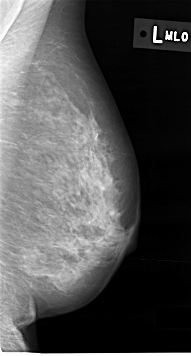

C_0012_1.LEFT_MLO

C_0012_1.LEFT_CC

LEFT_MLO LINES 4616 PIXELS_PER_LINE 2472 BITS_PER_PIXEL 12 RESOLUTION 50 NON_OVERLAY